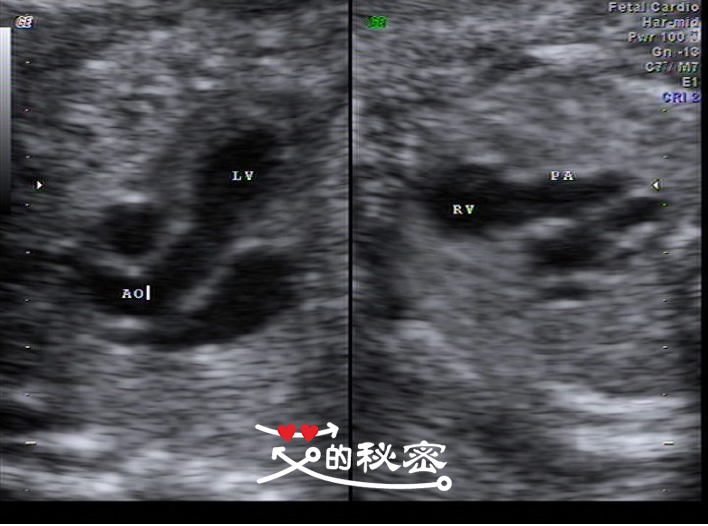

8、胎儿胸部:肺脏可见,心脏位置未见异常,心胸比例正常,心律整,由四腔心观“十”字结构存在,房室大小比例正常,卵圆孔及卵圆孔瓣可显示,左右房室瓣可显示,启闭好。流出道切面见主动脉与左室相连,肺动脉与右室相连。简写英文的意思LV左心室,AO主动脉,RV右心室,PA肺动脉。